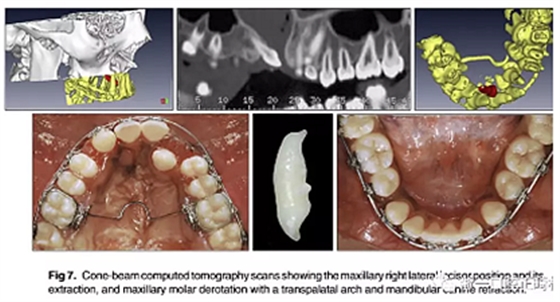

隨后,由口腔頜面外科醫(yī)生(圖6 ; 圖7)拔除左右側(cè)側(cè)切牙,并使用直角弓來旋轉(zhuǎn)上頜磨牙并改善牙弓形態(tài); 在下頜弓中,尖牙的牽引繼續(xù)(圖7)。